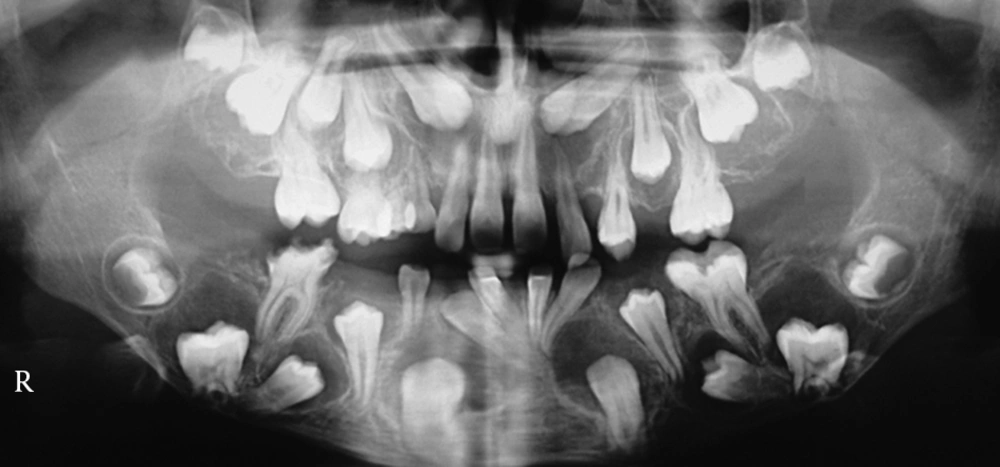

A 13-year-old boy with the chief complaint of multiple unerupted teeth was referred to department of Oral and Maxillofacial Surgery of Ahvaz University of Medical Sciences in May 2013. The panoramic radiograph revealed 15 unerupted teeth (8 in mandible and 7 in maxilla) with large pericoronal radiolucent zone (enlarged follicles) delineated by a well-defined sclerotic borders (Figure 1). Tooth abnormalities such as amelogenesis imperfecta were not seen. Medical and familial history was unremarkable and his siblings had normal dentition. The patient had normal intelligence. He did not have other signs and symptoms like cleidocranial dysplasia, Gardner syndrome, or mucopolysaccharidosis (three syndromes with tendency to multiple impactions). The incisional biopsy was performed with provisional diagnosis of Gorlin syndrome (multiple keratocystic odontogenic tumors). Microscopic examination revealed a dense and cellular fibrous connective tissue with numerous deposits of calcifications. Collagen fibers were arranged in whorled structures. Cords and islands of odontogenic epithelium with numerous clear cells were surrounded by these deposits. Calcifications were found in the whorled areas. There were many small circular droplets of basophilic calcified material resembling cementum. Most of the droplets were homogenous (up to 95%), but some revealed concentric layering similar to Liesegang rings of Pindborg tumor. The diagnosis was atypical follicles with odontogenic fibroma-like changes (WHO type) or hyperplastic calcified dental follicles (Figures 2- 4). Then, the excisional biopsy was performed for mandibular lesions. Grossly, the specimen consisted of multiple pieces of creamy brown soft tissues surrounding the crown of multiple extracted teeth totally measuring 5 × 5 × 1 cm. The lesions showed fine surface nodularities and produced a distinct grating sound during sectioning (Figure 5). The initial diagnosis has been confirmed. Additional surgical procedure must be performed for maxillary lesion in future.